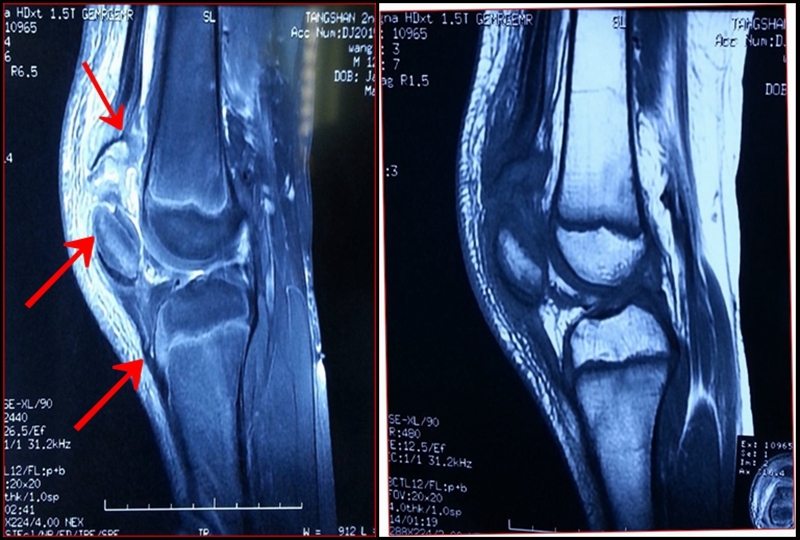

图3 受伤后3周MRI

考虑此患儿伤后已3周,组织全科讨论,确定诊断为:髌骨上极陈旧性套状撕脱骨折。充分与家属沟通远期预后。

1.髌骨上、下极的斑片、点状薄层骨组织影像或半环、新月形骨块阴影,同时还应注意髌骨有否高位、低位及髌韧带、股四头肌腱软组织影是否松弛。

2.X线片无骨性组织显影时,应予以MRI扫描。